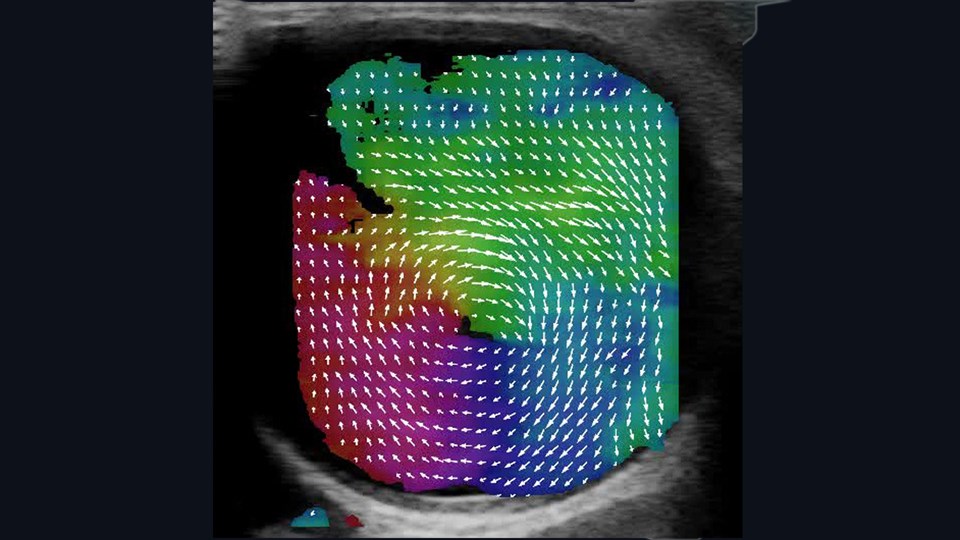

Diagnostic Imaging is focused on biomedical imaging, particularly translation between preclinical models and clinic. Specific research areas include biomedical imaging and biosignal analysis, MR and ultrasound imaging, radioisotopes and nuclear medicine, medical imaging computing. Below we have included examples of our activities in research related to Diagnostic Imaging.